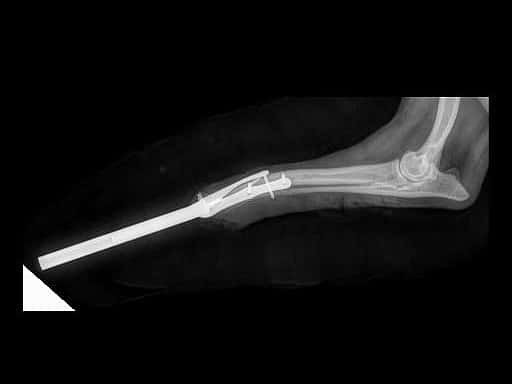

Lilly soffriva di una rara e complicata condizione chiamata "Ipogenesia dell’avambraccio destro", che aveva reso la sua zampa anteriore debole e inutilizzabile. Questa malformazione congenita aveva messo a dura prova la sua qualità di vita fin dall'inizio, ma la sua storia stava per prendere una svolta straordinaria. La missione di riportare Lilly alla sua piena vitalità è stata affidata a una squadra di professionisti eccezionali. Il Dottor Salvatore Maugeri, stimato ortopedico del gruppo AniCura, ha guidato l'equipe, assistito dal Dottor Rocco Freccia, esperto in chirurgia dei tessuti molli. La squadra intera di esperti non ha esitato a intraprendere un percorso ambizioso per restituire a Lilly la sua mobilità. Il primo passo nell'incredibile viaggio di Lilly è stata una simulazione avanzata di ingegneria tridimensionale computerizzata. Questa simulazione ha permesso agli specialisti di pianificare attentamente il processo e la forma della Protesi Intraossea Transcutanea (ITAP) che sarebbe stata realizzata appositamente per Lilly. Utilizzando la tecnologia di stampa 3D e titanio, è stata creata una protesi personalizzata per la giovane cagnolina, dimostrando il potenziale sorprendente

dell'ingegneria biomedicale moderna. Tuttavia, la sfida era solo all'inizio. La squadra medica si è trovata di fronte a diversi ostacoli da superare. La deformazione dell'anatomia di Lilly è stata affrontata attraverso un design e un layout della protesi impeccabili. Inoltre, il problema della lunghezza e delle sollecitazioni sulla zampa è stato attentamente gestito, assicurandosi che la protesi garantisse una distribuzione del peso uniforme e il comfort di Lilly. La mancanza di muscolatura, un problema comune in casi simili, è stata presa in considerazione, ponendo l'attenzione sull'articolazione omero-ulnare e sul legamento olecranico per assorbire le

sollecitazioni in modo appropriato.